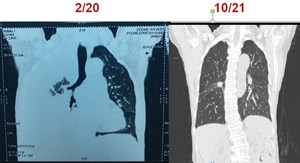

Sử dụng hiệu quả thuốc nhắm trúng đích EGFR-TKI thế hệ 3 cho bệnh ung thư phổi giai đoạn cuối (7/4/2023)